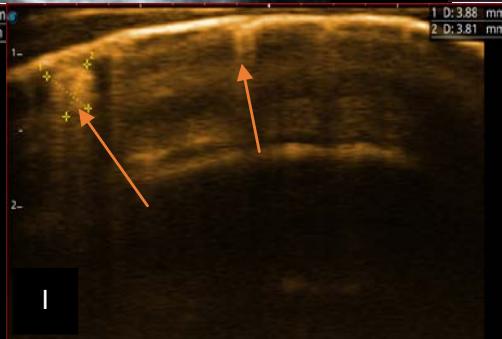

Figure 6: 9-year-old sickle cell patient, referred for abdominal bloating with significant collateral venous circulation, in whom we noted: Image A: mass, Image B: healthy renal stump, inferior polar; Image C: left transmedian extension, Image D: thrombosis of the vena cava segments: supra, retro and sub hepatic, sparing a part of the supra hepatic vena cava segment over $30~\mathrm{mm}$. Image: Ascites of great abundance, Image F: normal left kidney, Image G: splenic microcalcifications, Image H: celiac adenopathy, Image I: sub pleural pulmonary nodules with the biggest measuring $3.88 \times 3.81 \mathrm{~mm}$, Image j: left pleurisy of great abundance. Source: Dr. Frederick Tshibasu Tshienda database.